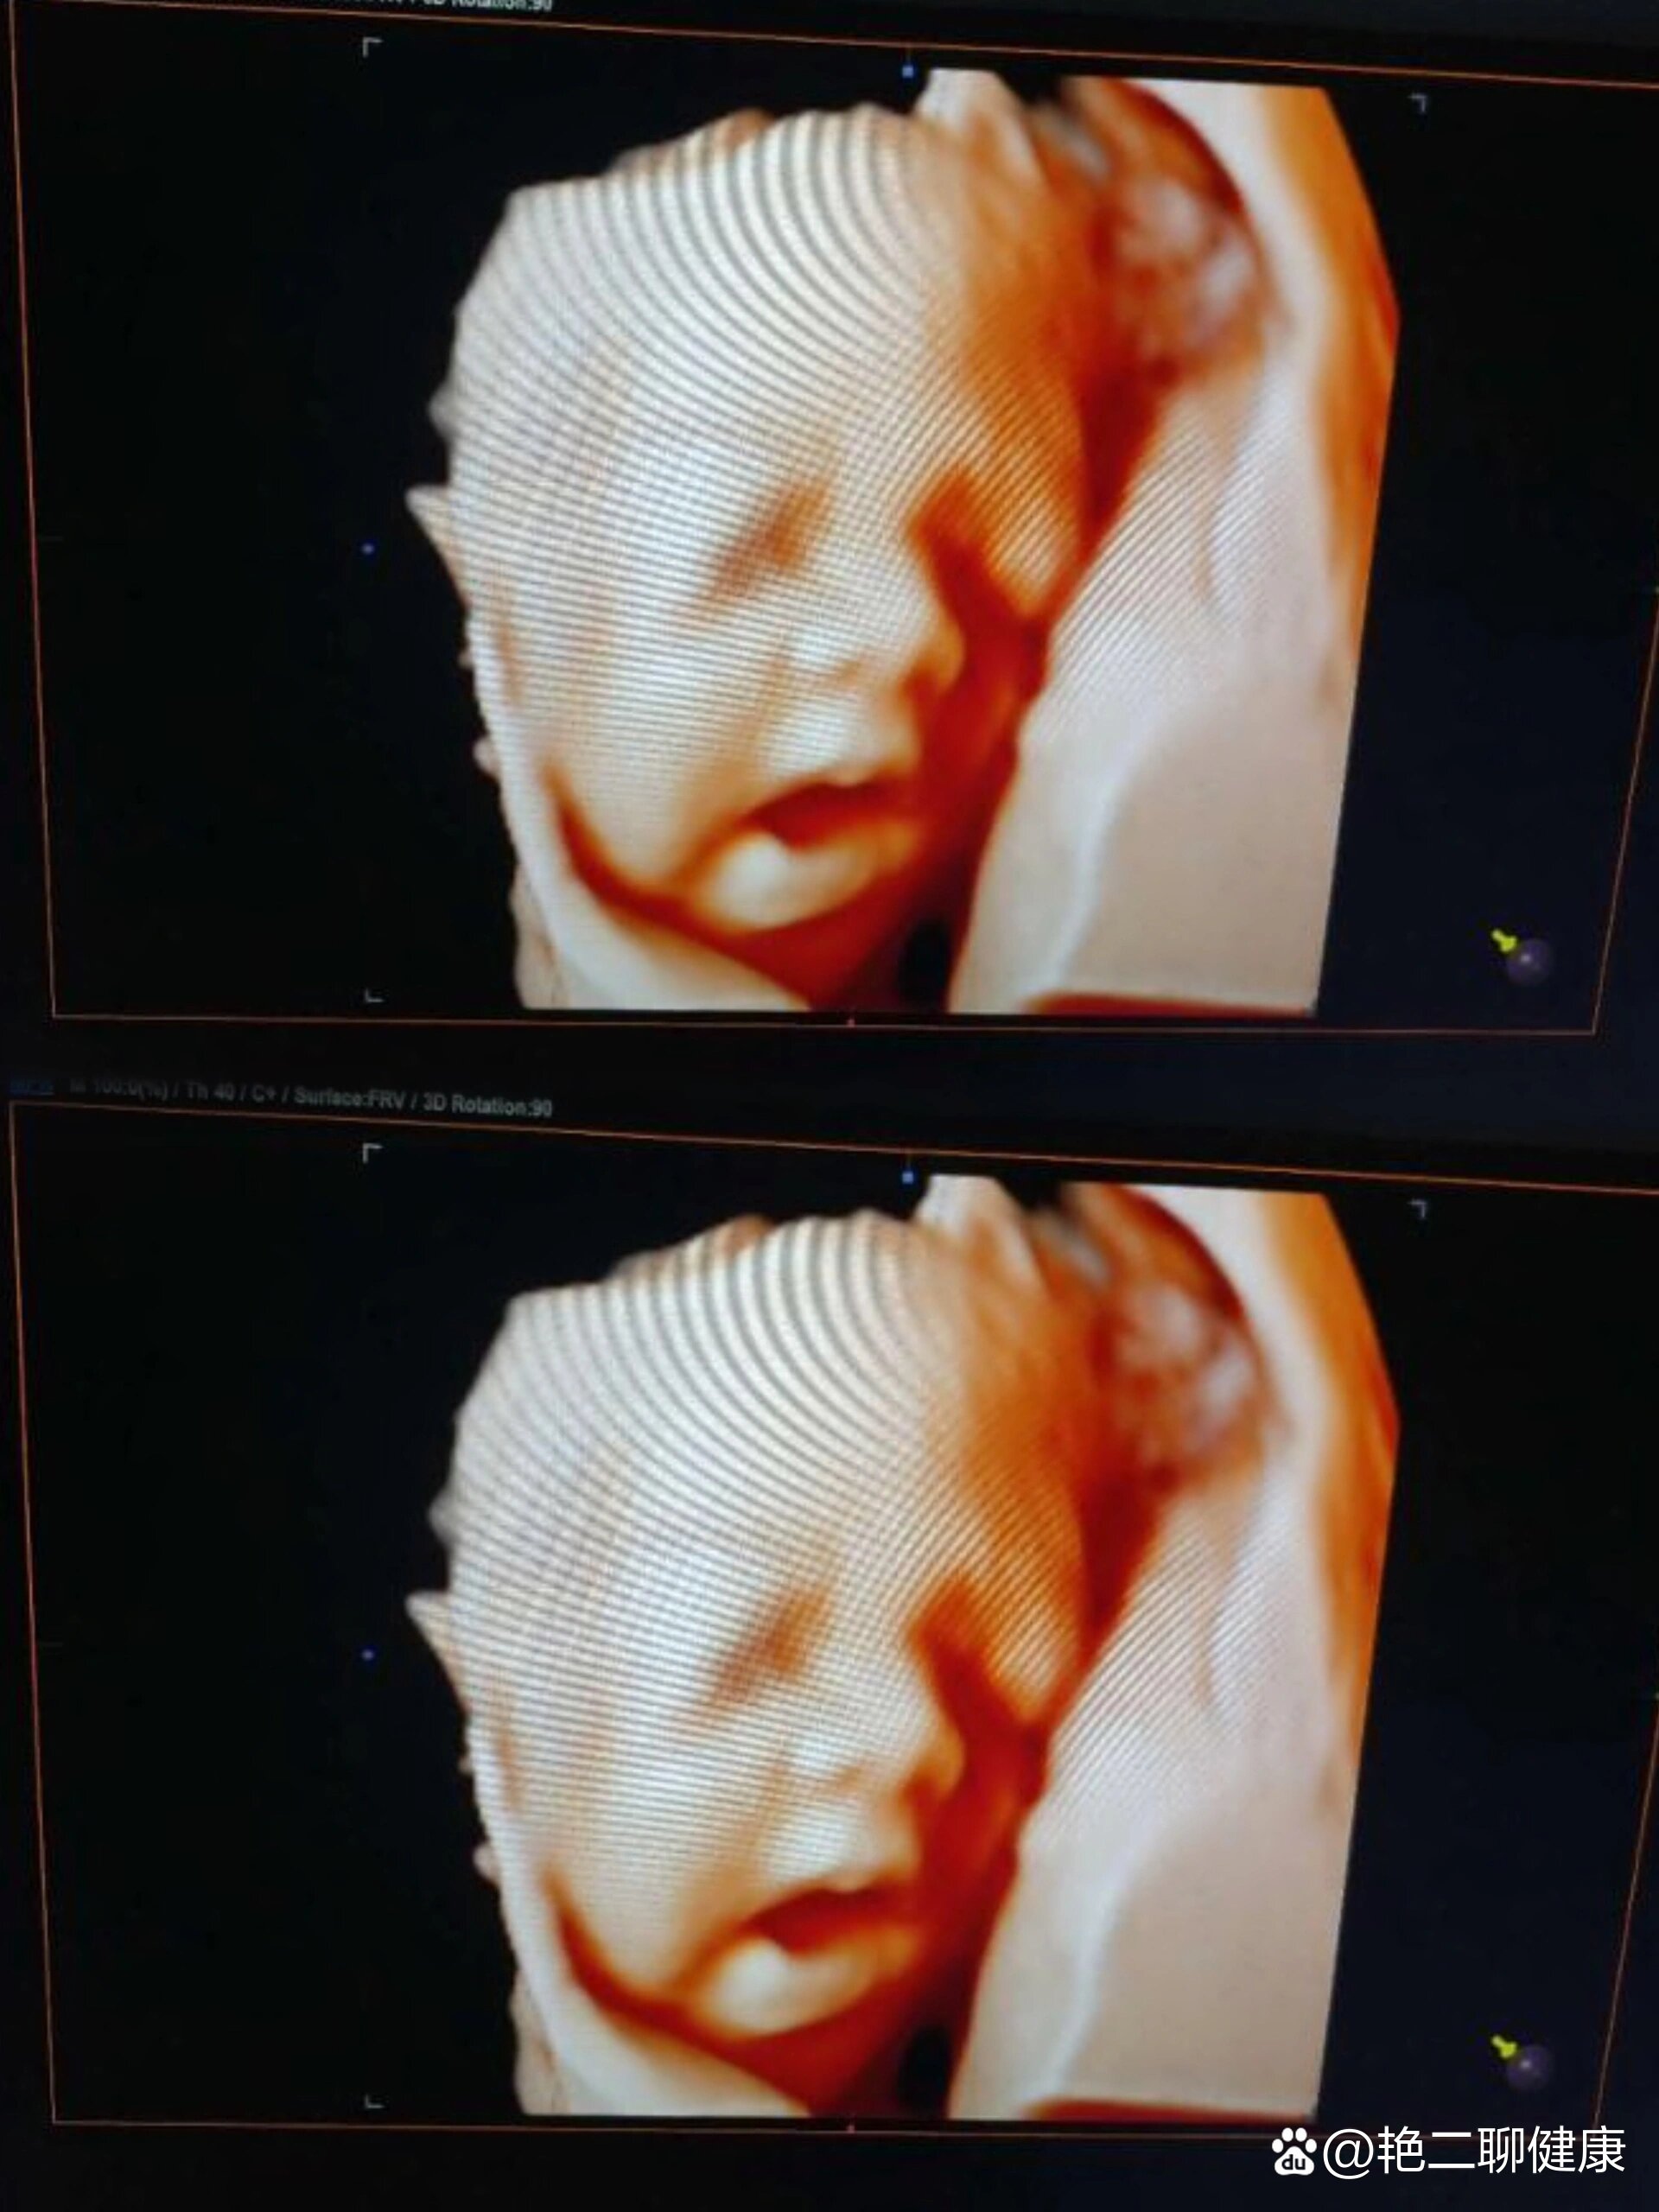

怀孕5个月通常可以做四维彩超以下是关于四维彩超的详细科普一检查的适宜时间及意义妊娠2024周即怀孕56个月是四维彩超的最佳检查时间此时胎儿大小适中,羊水比例适宜,胎儿在子宫内的活动空间充足,便于医生清晰观察胎儿的各个脏器面部及肢体结构此时胎儿大部分器官已发育成形,通过四维彩超。

五个月胎儿可以做四维彩超,且此时是适宜的检查时间一检查的可行性及意义怀孕五个月约2024周时,胎儿各器官已基本发育成型,具备清晰的解剖结构,且子宫内羊水充足,为超声检查提供了良好的声窗条件四维彩超通过动态成像技术,可实时观察胎儿活动及器官形态,目前无科学证据表明该孕周进行四维彩。